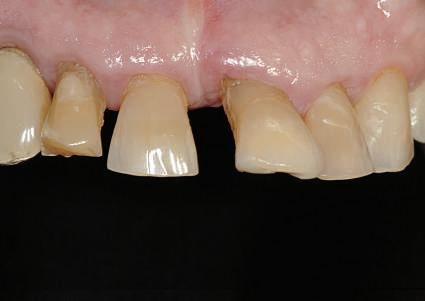

Dacă însă implanturile sunt plasate prea vestibular sau prea superficial, componentele nu permit un design adecvat al bontului, pentru că plasarea marginii este limitată iar conturul facial şi proximal poate fi compromis (fig. 1, 2).

Figurile 1, 2. Compromisurile conturului vestibular şi proximal sunt evidente. Implantul este la nivel tisular, tehnicianul neputând gestiona plasarea marginii sau a profilului intrasulcular pentru a îmbunătăţi estetica. Dacă se concepea un design tradiţional cu hexagon extern, marginea restauratoare s-ar fi putut plasa foarte aproape de interfaţa bont-implant, cu gestionarea mai bună a spaţiului.